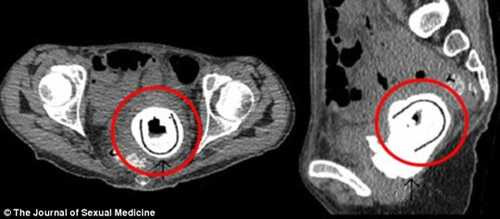

Dị vật được xác định là đồ chơi tình dục có chiều dài khoảng 11 cm. Người phụ nữ này cũng thú nhận đã đưa món đồ chơi "người lớn" này vào trong âm đạo khi quan hệ với bạn tình từ 10 năm trước đây lúc đang say rượu nhưng không nhớ mình đã lấy nó ra hay chưa.

Vật thể này đã khiến cô bị tắc nghẽn đường tiết niệu và rò rỉ bàng quang. May mắn thay, các bác sĩ đã phẫu thuật lấy dị vật ra khỏi cơ thể người phụ nữ thành công.

Theo Tạp chí Y học tình dục, đây là trường hợp đầu tiên đồ chơi tình dục bị mắc kẹt trong cơ thể con người lâu đến vậy.

| Đồ chơi tình dục trong vùng kín người phụ nữ |